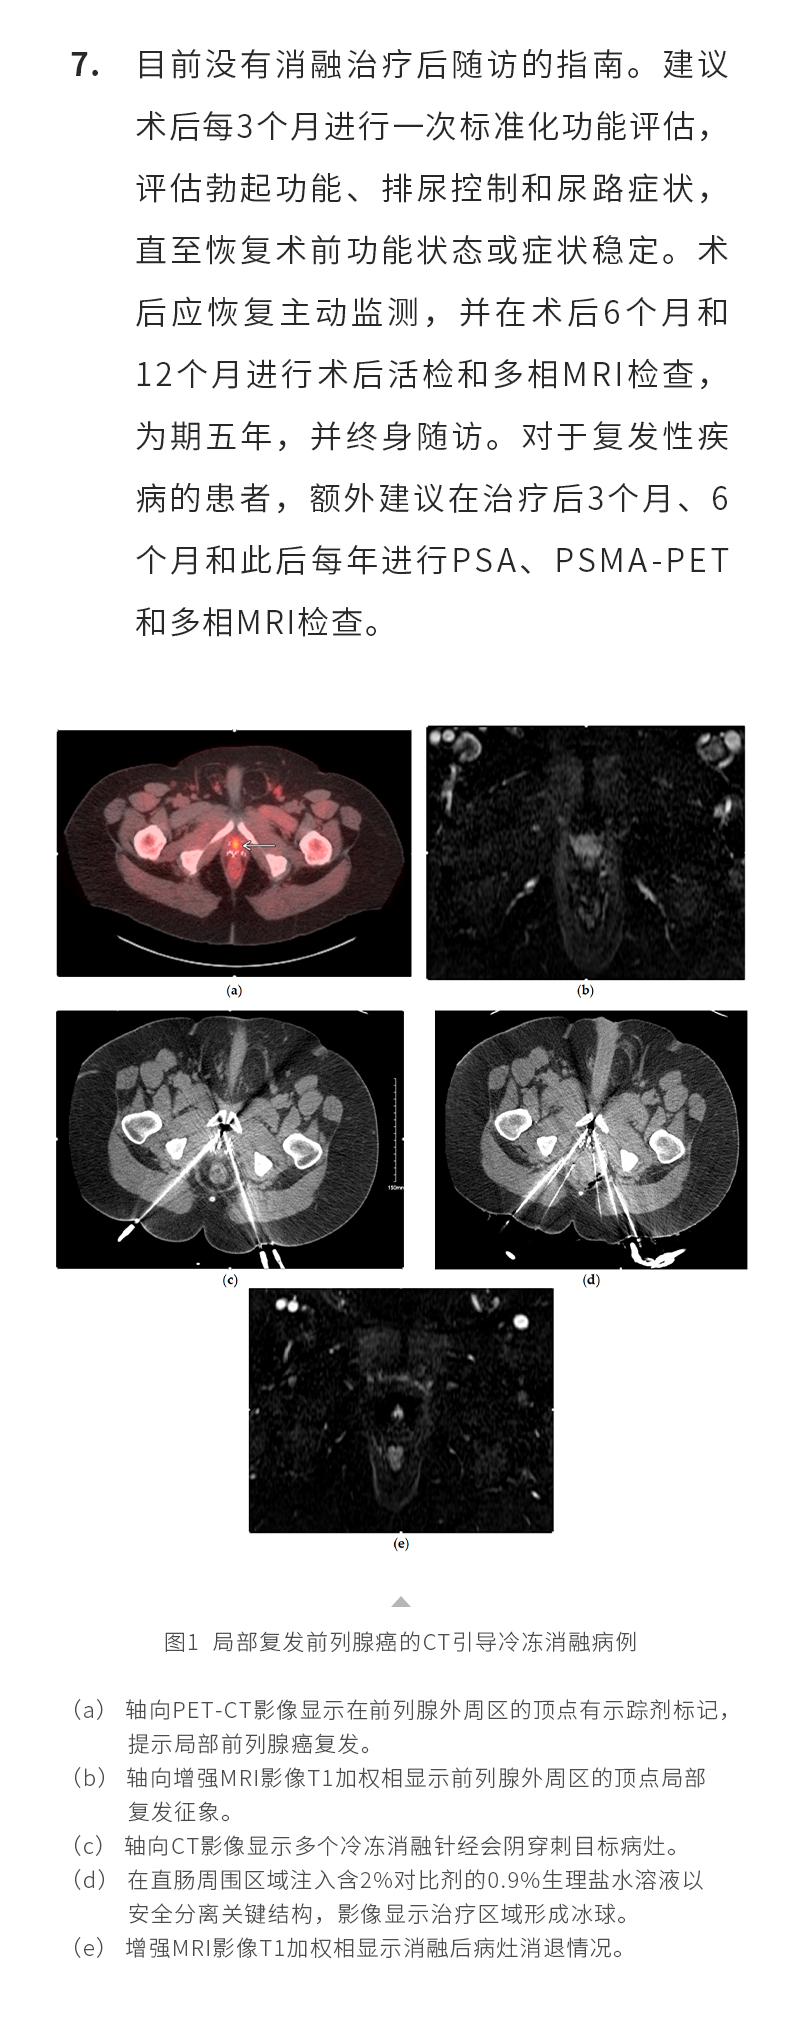

聯系我們